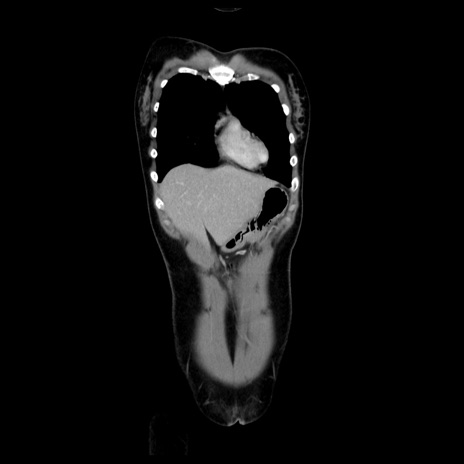

症例39(冠状断像)

【症例】40歳代女性

【主訴】上下腹部痛

【現病歴】2日目から下腹部痛あり。夜間は痛みで眠れなかった。昨日より上腹部痛と下痢が出現。臥位で痛みは軽快したため、休んでいた。本日になって臥位でも立位でも痛みが強くなってきたため救急要請。

【既往歴】子宮内膜症

【身体所見】部:平坦・軟、左上下腹部に圧痛あり、反跳痛あり。

【データ】WBC 21800、CRP 26.78

CT